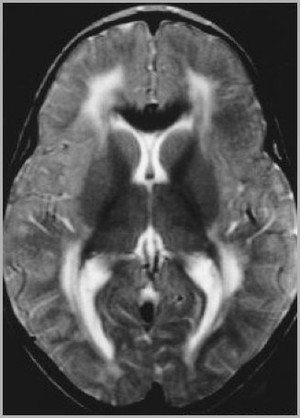

A 45 year old man with a 20-year diagnosis of HIV is brought to the physician by his partner after he notices cognitive changes in his partner. On neurological exam, the physician notes unilateral weakness. An MRI is ordered that reveals the following changes. What is the patient’s probably diagnosis given his presentation and underlying conditions?

Progressive multifocal leukoencephalopathy:

JC virus is a polyoma virus that causes a lytic infection of oligodendrocytes in immunocompromised persons.

70-80% of adults worldwide are seropositive for JC virus.

- Patients with compromised immune status especially AIDS patients are at risk for PML.